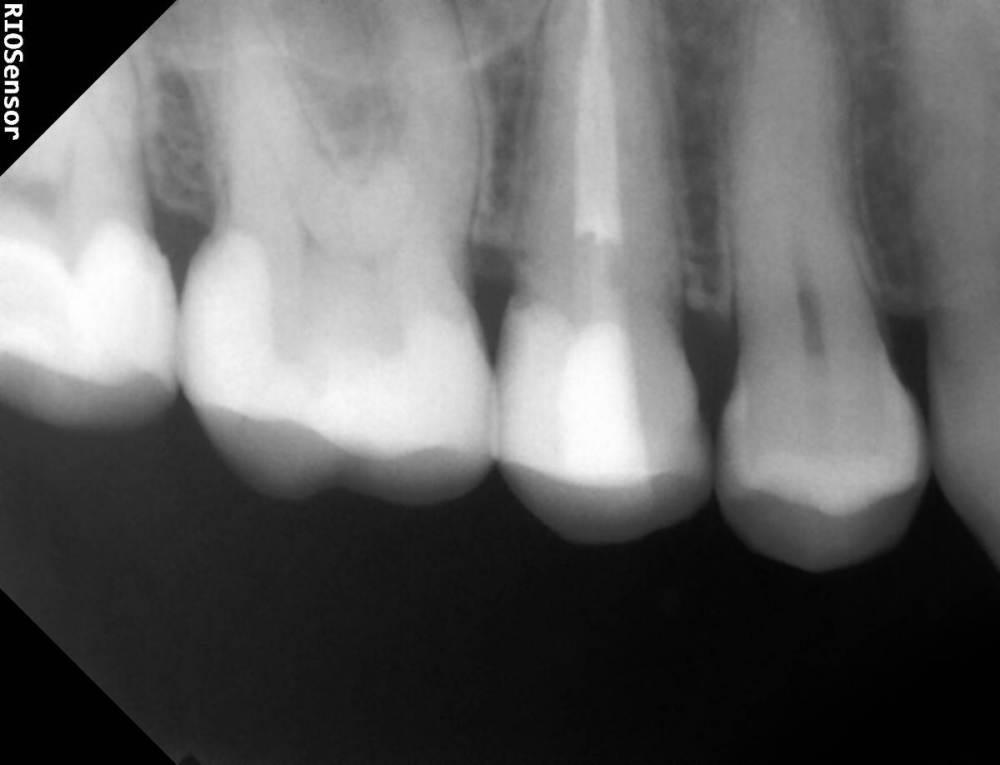

Александра117 Опубликовано 19 ноября, 2022 Поделиться Опубликовано 19 ноября, 2022 Всем Привет! Месяц назад лечила зуб верхнюю 5ку. Депульпировали и Пломбировали каналы гуттаперчей. На момент лечения в зубе уже была боль. Был поставлен диагноз пульпит. Но прошел уже месяц и боль в зубе сохраняется , при этом почти точно такая же как и до лечения. Боль постоянная ноющая средней интенсивности. Я думала это первое время после лечения такая боль будет. Но месяц прошел, а боль не уходит. Немного предыстории этого зуба: Зуб этот меня вообще не беспокоил изначально. Я пришла 12.09.2022 на прием, чтобы вылечить кариес. Стоматолог рассверлил и запломбировал. Но сказал, что очень глубокий кариес был, но решил пока сохранить пульпу и наблюдать. После лечения появились боли в зубе ,но терпимые. Через две недели боли усилились. Я пришла на прием снова с этим вопросом. Врач сказал, что после лечения глубокого кариеса могут быть боли, надо ещё понаблюдать. Ещё через пару неделю боль не проходила. Была довольно сильной. Врач принял решение депульпировать зуб. Лечение я проходила под микроскопом у опытного эндодонтиста. Именно у него я уже до этого лечила каналы у нескольких других зубов, и все было нормально. Но также это в в первый раз такое случилось, что боли такие сохраняются в течение месяца после лечения. После лечения врач сказал, что зуб меня беспокоить не должен больше. Сказал, что было лечение неосложненного пульпита. Но он беспокоит вот уже месяц. Вообще это у меня впервые, чтобы была боль в зубе и на момент лечения и после лечения каналов. До этого до болей в зубе дело не доходило. Пролечивалось раньше. Сделала свежие снимки Рентен через месяц после Лечения, их прилагаю сюда. По снимку видно, что каналы пройдены полностью до конца. Материал за Пределы Корня не выведен. Найдены все каналы. Их у меня в верхних пятерках их по два. Как и видно по КТ. Скажите, что это может быть? И что Можно сделать? Требует ли эта ситуация какого то срочного вмешательства или можно ещё наблюдать? Может ли это быть периодонтит, при том что на снимке в прикорневых тканях все спокойно? Ещё на внешней стороне зуба есть две белые трещины. Как раз на границе пломбы и стенки Зуба. В этом месте если трогать языком очень шершавая поверхность. Также, можете сказать, эти трещины это трещины Эмали или может быть что и более глубокие Трещины? ( Фото трещин тоже прилагаю) Ссылка на комментарий

Doc Опубликовано 19 ноября, 2022 Поделиться Опубликовано 19 ноября, 2022 А какого характера боли? Самопроизвольные, на холодное-горячее, острые или не очень, ночные-дневные, длительные или кратковременные? Это может иметь диагностическую ценность. Между пятеркой и шестеркой на снимке есть подозрение на кариес корня, но по этим снимкам сложно сказать что-то определенное. Ссылка на комментарий

Doc Опубликовано 20 ноября, 2022 Поделиться Опубликовано 20 ноября, 2022 На пятерке почти точно, на шестерке сложно сказать по этому снимку, но подозрение есть тоже. Если там есть кариес корня, то он вполне может перейти в пульпит и так болеть. Ссылка на комментарий